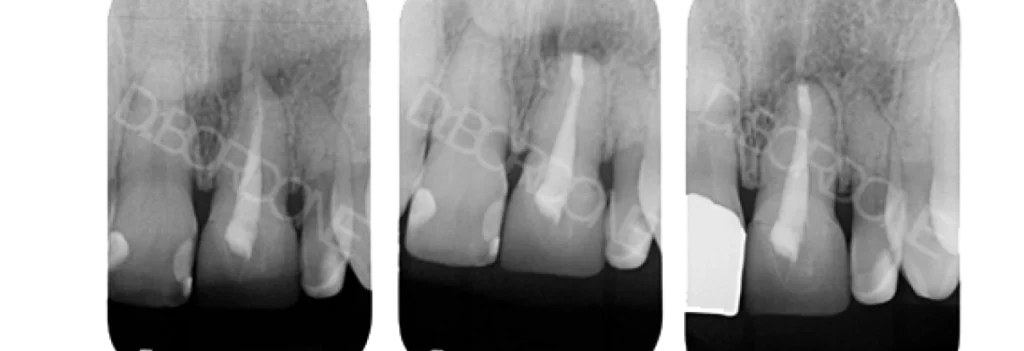

Exemple d’une chirurgie endodontique et guérison à 1 an :

chirurgie endodontique marseille Résection apicale Dr Antonietta BORDONE - Endodontiste à Marseille